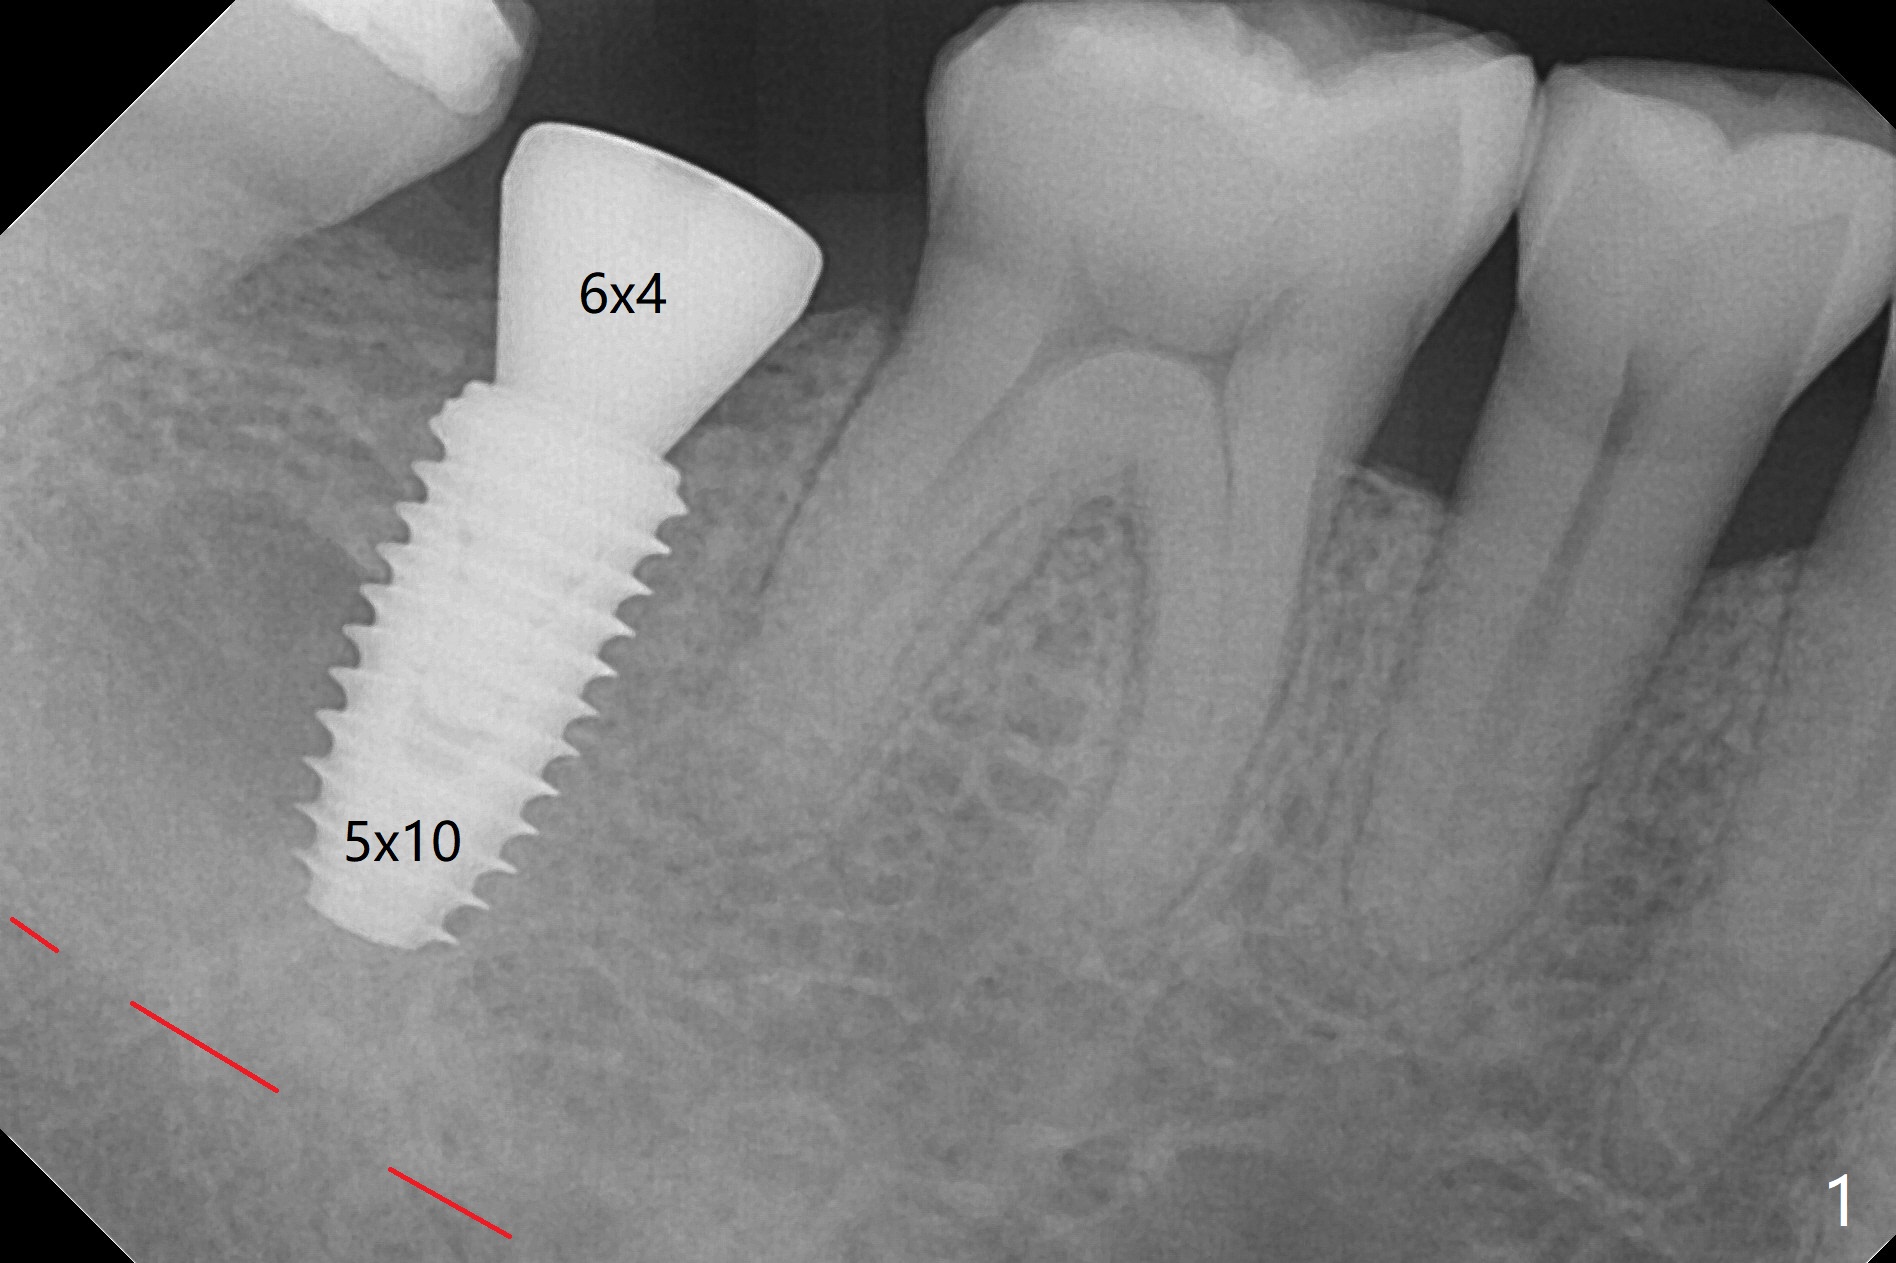

In fact 5x10 mm implant placement with guide requires using 5 mm cortical tap (Fig.1). When a 6x4 mm healing abutment is placed slightly supragingival, the clearance with the opposing supraerupted tooth is ~ 2 mm. It suggests that orthodontic intrusion is required for restoration. In fact the patient is incompliant with orthodontic mini-implant placement and retraction. When the implant at #31 is osteointegrated 4.5 months postop (Fig.2), it is used an anchor with an abutment and a provisional to intrude the opposing tooth. The final crown is cemented 10 months postop (Fig.3) with occlusal clearance (Fig.3' *). The contacts between #2 and 3 and between #31 and 32 are loose with papillary inflammation 5 months post cementation. It is planned to remove #31 crown/abutment for pick up impression/porcelain addition. Instead the crown is removed. After removing #32 MO composite with minor 2nd caries, new composite is placed (Fig.4 *) while the crown is reseated. When the crown is recemented, bitewing shows open margin (Fig.4), but the contact is wide and tight. After occlusal adjustment, occlusal contact at #31 and 32 mesial is heavier than that at #30. #3 crown is recommended. The occlusal table difference betweeen the upper 1st and 2nd molar is ~ 2 mmm preop (Fig.4'), whereas the difference is ~ .6 mm postop (in combination of occlusal equilibrium and intrusion of the upper 2nd molar (Fig.4)). It seems that orthodontic intrusion is not efficient in a male with bruxism. There is mild lingual (L) and distal bone loss 1.5 years post cementation (Fig.5) when CT is taken for #3 immediate implant. Lower Molar Immediate Implant, Armaments Xin Wei, DDS, PhD, MS 1st edition 07/12/2018, last revision 11/28/2020